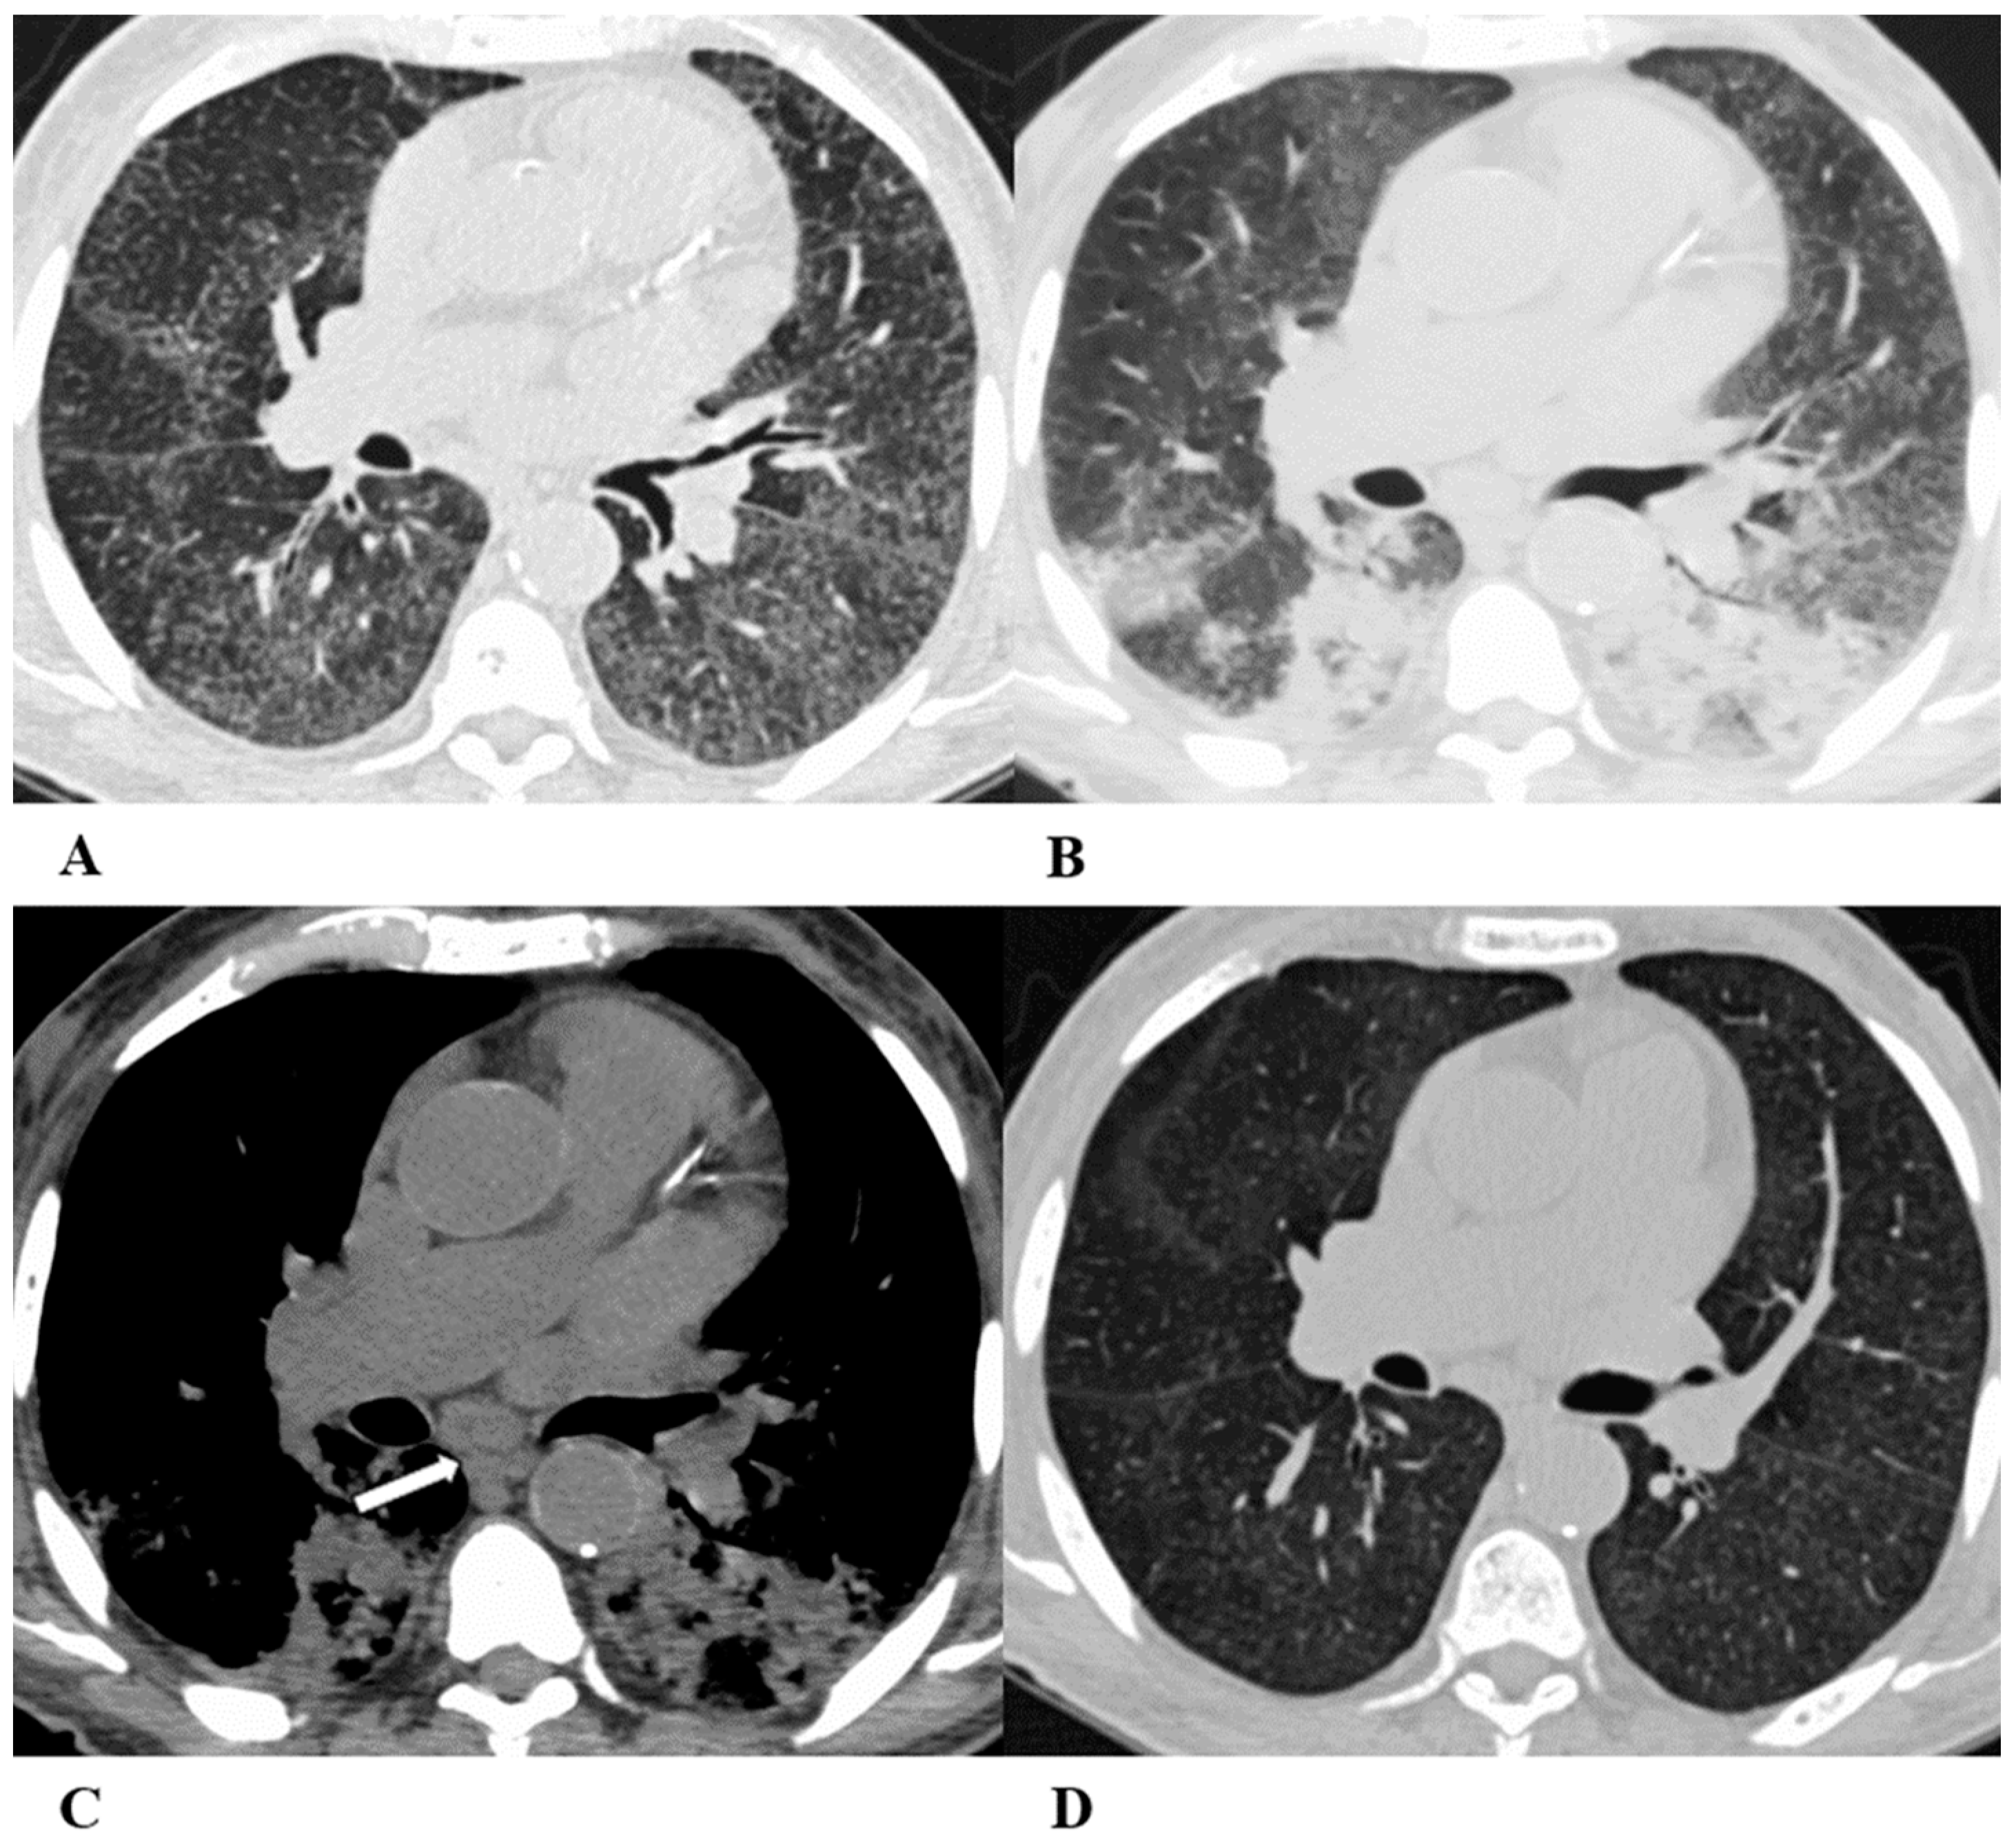

Figure 4.

Acute interstitial pneumonia (AIP)/acute respiratory distress syndrome (ARDS). Acute interstitial pneumonia (AIP) and acute respiratory distress syndrome (ARDS) can be a consequence of both pathogenic intrapulmonary and extrapulmonary stimuli. They are clinically characterized by acute respiratory failure, a consequence of alveolar thickening due to hyaline membrane deposition and inflammatory cells’ infiltration. Both conditions likely represent the same pathology, with AIP probably accounting for some of the idiopathic cases of ARDS.

ARDS from extrapulmonary disease shows bilateral symmetrical changes on CT, whereas in pulmonary ARDS, the opacities tend to be asymmetrical.

The initial form of ARDS can also be classified as diffuse alveolar damage (DAD), followed by the organizing and delayed phases.

HRCT features depend on the phase of the disease, with the possibility of GGOs in the acute phase, and lung cysts and pulmonary opacifications often with an anteroposterior gradient in the delayed phase; complete resolution or evolution into a coarse reticular pattern, traction bronchiectasis and possible bullae, as result of prolonged ventilation, may be found. Sometimes, pleural effusion is observed [9,12,16].

(A–D) A 45-year-old man with rectal carcinoma metastatic to the liver, treated with pembrolizumab. After nearly three months of immunotherapy, the patient suffered acute respiratory failure and interstitial pneumonia suggestive of ARDS in the clinical setting.

Baseline axial chest CT scans (A,B) showed numerous partially confluent areas of GGO, more represented in the perihilar regions as a result of extensive alveolar damage (white arrow), with some dependent asymmetrical peripheral consolidations (black arrow) like an early ARDS pattern, which made it necessary to hospitalize the patient in the intensive respiratory care unit with nose–tracheal intubation.

Three weeks later, CT images (C,D) demonstrated lung architecture disruption, a large component of GGO, reticulation with areas of crazy-paving (black arrowheads), incremented consolidation in the dependent lung and traction bronchiectasis, as seen in the delayed fibrotic ARDS phase.

As accessory findings, note the altered profile of the right ventricle outflow tract (RVOT) and pulmonary trunk with wall calcifications, as a result of multiple reconstructive operations in pediatric age for tetralogy of Fallot.